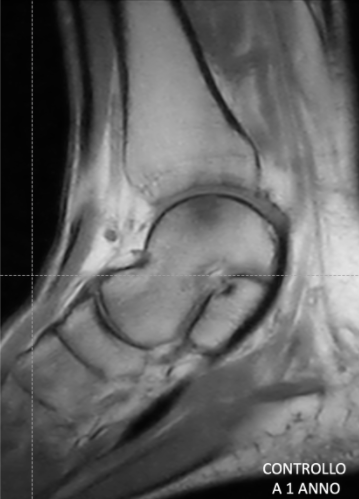

MRI check-up one year after surgery